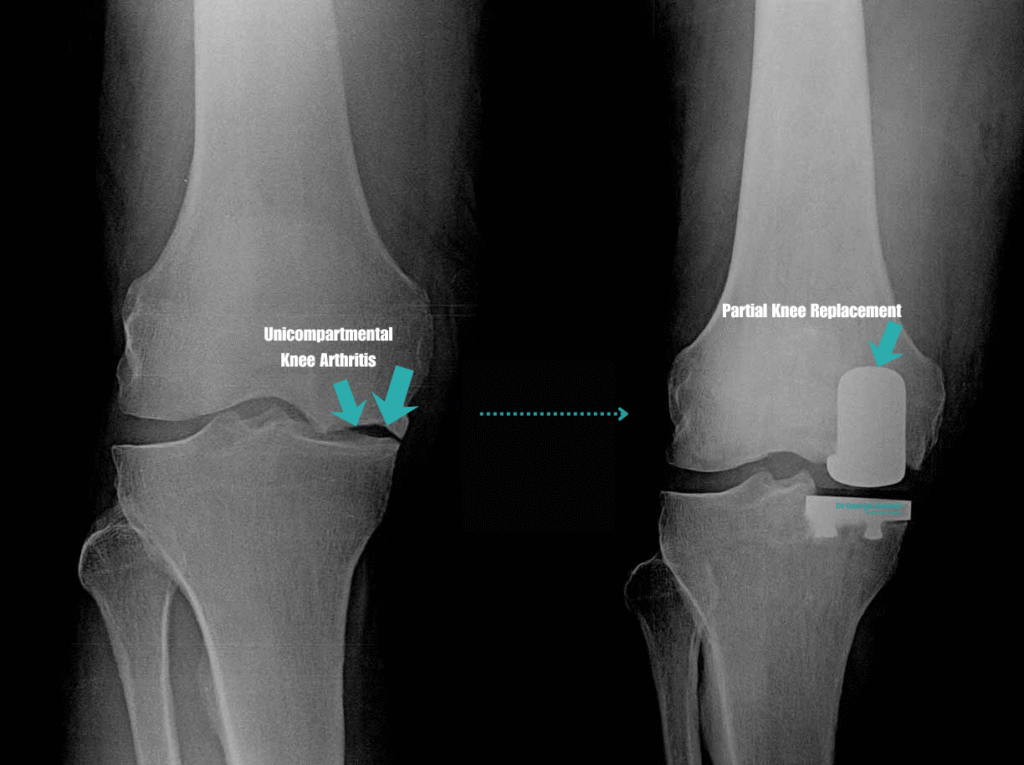

Partial knee replacement surgery, also known as unicompartmental knee arthroplasty, is a surgical procedure used to treat arthritis that affects only one part of the knee joint. Unlike total knee replacement, which replaces the entire joint surface, a partial knee replacement involves resurfacing only the damaged compartment, typically the medial (inner), lateral (outer), or patellofemoral (kneecap) region, while preserving healthy bone, cartilage, and ligaments.

A partial knee replacement, also known as unicompartmental or, hemi knee arthroplasty, is a surgical procedure used to treat arthritis or damage that is limited to a single compartment of the knee joint. Unlike a total knee replacement, which replaces all the surfaces of the knee, a partial knee replacement targets only the affected area, either the medial (inner), lateral (outer), or patellofemoral (kneecap) compartment.

How is partial knee arthritis different from total knee arthritis?

Knee arthritis does not always affect the entire joint. In many patients, the wear and tear is isolated to a specific region, or “compartment,” of the knee. Understanding the difference between partial and total knee arthritis can help clarify whether a partial knee replacement may be a suitable surgical option.

Partial knee arthritis (unicompartmental disease)

Partial knee arthritis occurs when the degenerative changes are limited to just one of the three main compartments of the knee:

- Medial compartment (inner side of the knee)

- Lateral compartment (outer side)

- Patellofemoral compartment (behind the kneecap)

In these cases, the other compartments of the knee remain healthy, and the supporting ligaments such as the ACL and PCL are still functioning. Patients with partial knee arthritis often experience pain, stiffness, or swelling that is localised to one side of the knee or behind the kneecap, rather than throughout the entire joint.

Why this distinction matters

The type and distribution of arthritis in your knee is a major factor in determining which treatment is most appropriate. If arthritis is isolated and the rest of the knee is well-preserved, partial knee replacement may be considered. This allows preservation of natural structures and may offer a quicker recovery and more natural knee feel after surgery.